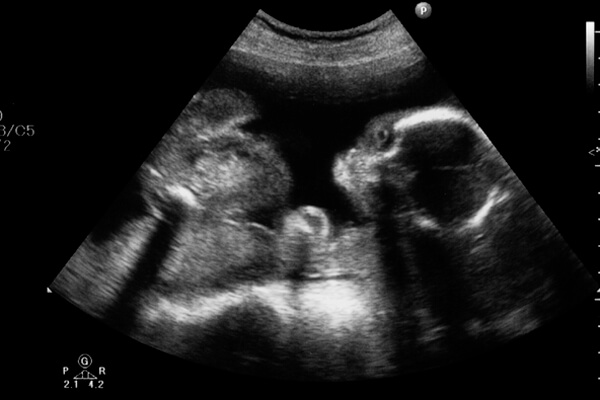

妊娠21週目は妊娠中期である妊娠6ヶ月の2週目にあたります。ママはお腹やおっぱいが大きくなり、より妊婦さんらしい体つきになってきます。

お腹の中の赤ちゃんは、体も脳も急速に成長してきて活発に動き回っています。今回は、妊娠21週目(妊娠6ヶ月)のママと赤ちゃんの様子をご紹介します。

妊娠21週目(妊娠6ヶ月)の赤ちゃんの身長は19〜25cmくらい。体重は300〜450gほどで3頭身くらいです。指は、物をつかめるまでに発達しています。

子宮が大きくなり羊水の量が増えるので、赤ちゃんは羊水の中で自由に動き回っています。

赤ちゃんは羊水の中で大きく回転するような動きをしていますので、逆子になっている場合もありますが、この時期の逆子はまだ心配しなくても大丈夫ですよ。

この時期にエコー検査で、赤ちゃんの性別が判明するかもしれませんね。